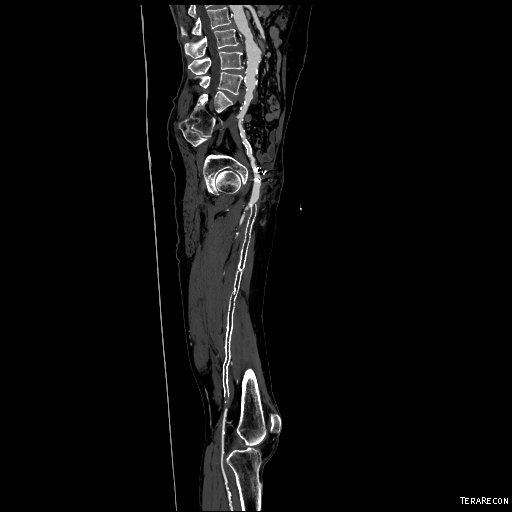

Let me show you one of the first cases I did after returning to Cleveland. I am now practicing at Fairview and Avon Hospitals, premier flagship hospitals in the Cleveland Clinic fleet, on Cleveland’s west side, and a patient arrived while I was on call with sudden onset of pain in his leg from a lack of blood flow. He had occlusive atherosclerotic plaque extending from his external iliac artery to the above knee popliteal artery causing ischemic rest pain.

I contacted LeMaitre Vascular and got in touch with your representative, L. Fisher, who promptly sent the Moll Ring Cutters I needed to perform a remote endarterectomy of the patient’s occlusive external iliac and superficial femoral artery plaque. The technical details of remote endarterectomy are have been covered in my blog (https://vascsurg.me/?s=endore), but in the end, through a 7cm incision in the groin (don’t believe the hype, this is minimally invasive), I restored his arteries to their original open condition. Shown below are the results. It was with great sadness that I heard that the LeMaitre Vascular equipment being sent were the last of the stock available in North America. The patient did very well, with the operation completed well before lunch, and is recovering rapidly from his small wound and big rescue. He gets to walk out of the hospital on two legs, but also with the surety that he avoided a major bypass operation, and avoided the short term gains of stenting from the aorta to the profunda -more peel packs and landfill items and a dubious long term durability. Hey, I even used a XenoSure patch on the common femoral.